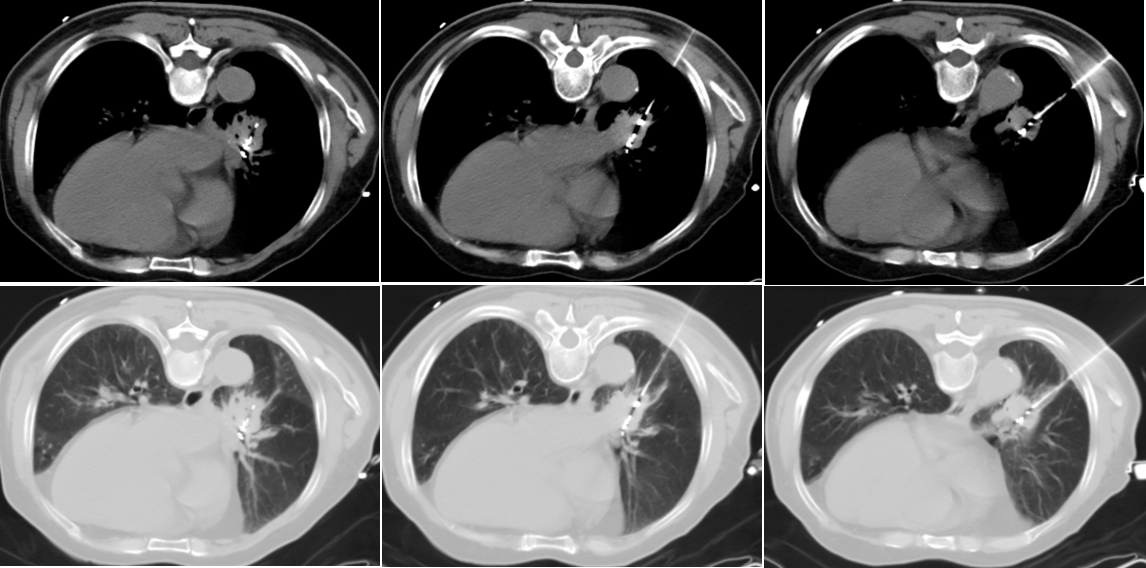

该患者男性,长期吸烟因咳嗽咳痰至医院复查被确诊为小细胞肺癌晚期(IVA期),肿瘤扩散到了周围多个淋巴结并转移到肋骨,患者体力评分1分,外院多疗程化疗后拒绝外放疗。经戈霞晖主任医师团队充分评估与讨论,决定为其进行肺内病灶碘125粒子近距离组织间植入术。手术依据TPS计划,在实时CT影像引导下,将放射性碘125粒子精准植入肿瘤内部。

戈霞晖介绍:放射性碘125粒子植入,属于近距离放疗的治疗方法,也是一种肿瘤介入治疗的常见方法。该方法主要利用放射性粒子源持续发出低剂量的γ射线,使肿瘤组织遭受最大程度的辐射损伤和破坏,而对正常组织影响很小,从而精准有效的对局部肿瘤起到治疗作用。目前主要应用于复发、难治恶性肿瘤治疗,具有微创、副作用少、消瘤效果好、精确性高等优势,其在临床应用广泛。